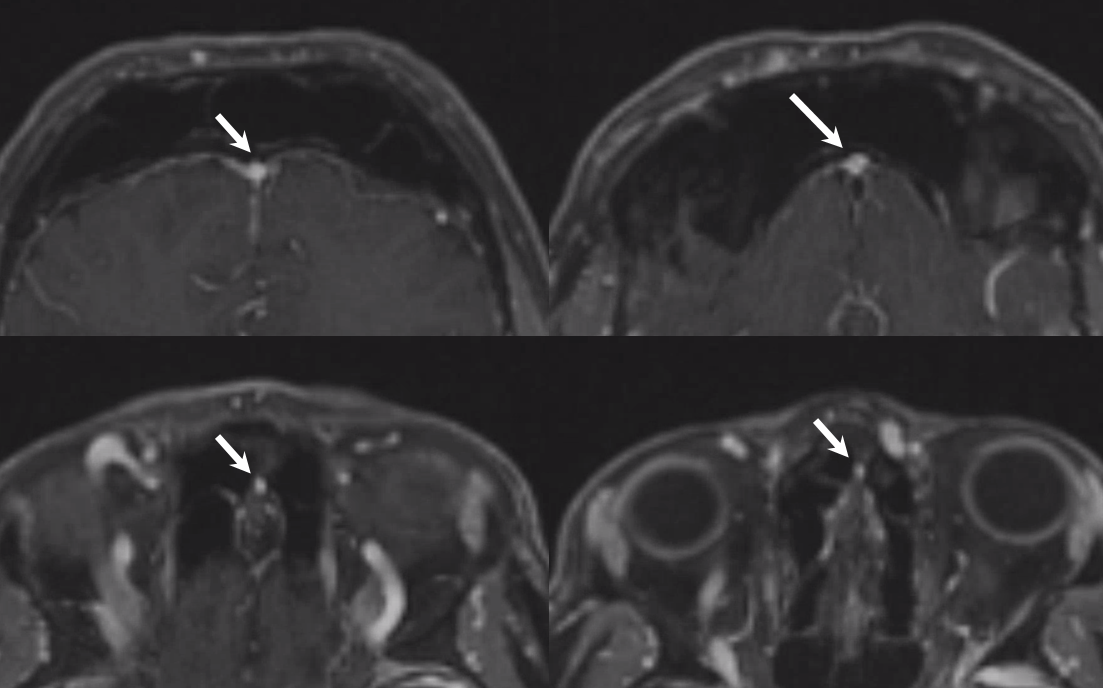

The general neurosurgical fact that the anterior third of the superior sagittal sinus can be safely sacrificed is true almost all the time. When it is not, consequences can be catastrophic. Normally, few veins drain into the anterior 3rd of the SSS, and these usually have collaterals. However, occasionally a large frontal or sylvian vein happens to drain anteriorly. Taking this sinus means risking a venous infarct. Here is an extreme example of dominant inferior left frontal vein draining into the anterior third of the frontal sinus, on MRI. Case courtesy Dr. Howard Riina

Angio is much easier to appreciate. It is well to learn how to spot these veins on MR or CT, as most patients don’t get presurgical angiography for nonvascular lesion